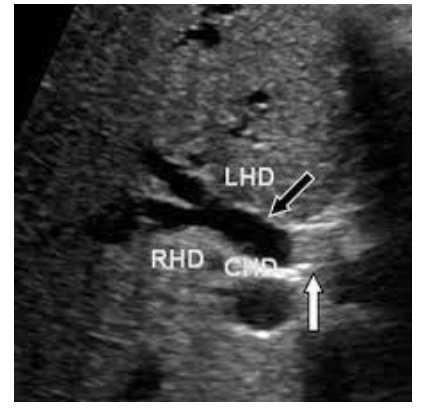

What pathology is found below?

Distal cholongiocarcinoma

Focal irregular ductal construction, wall thickening